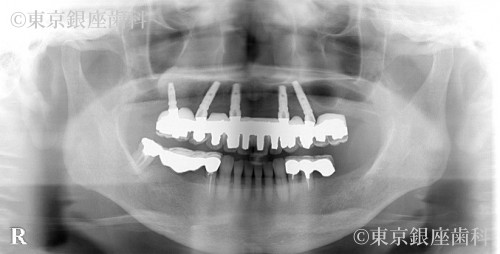

複数の奥歯を長期間失い、前歯に過度な咀嚼力の負担がかかってしまったため、全顎的にインプラントを支台とした口腔機能回復が必要となった症例

今回の症例に関しては、上顎は全顎的な口腔機能の回復が必要で、右側の奥歯は骨の吸収が大きかったためサイナスリフトを並行して行いました。

下顎はかぶせ物の治療で十分な咀嚼機能の回復をえることができました。